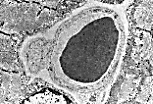

Observation en M.E.T.

Coupes transversales

Cette section transversale passant en dehors du noyau de la cellule endothéliale montre la membrane basale, le cytoplasme de la cellule endothéliale et un globule rouge occupant toute la lumière.

Cette autre coupe est réalisée au niveau du noyau de la cellule endothéliale. Celui-ci épouse la courbure du capillaire.

La lumière du capillaire est occupée par des protéines plasmatiques qui ont précipité lors de la fixation.

Le péricyte est une cellule accolée au versant exoluminal de l'endothélium dans un dédoublement de la lame basale.

Cette C.T. montre le noyau  incurvé de la cellule endothéliale, le cytoplasme endothélial empli de vésicules de transcytose, la jonction des bords libres de la cellule endothéliale, la membrane basale et dans un dédoublement de celle-ci, un fragment de cytoplasme de péricyte.

Cet agrandissement détaille la jonction cellulaire de type tight, les vésicules de transcytose.

Ces vésicules témoignent d'un transport transcellulaire important au sein des cellules endothéliales.

Le pli marginal, évagination cellulaire souvent située au niveau de la jonction, jouerait un rôle hydrodynamique.